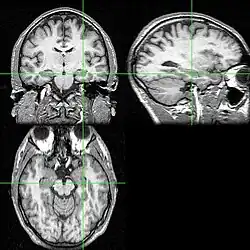

Diversos cortes de ressonância magnética com a localização do hipocampo (cruzamento das linhas verdes).

Diversos cortes de ressonância magnética com a localização do hipocampo (cruzamento das linhas verdes). -